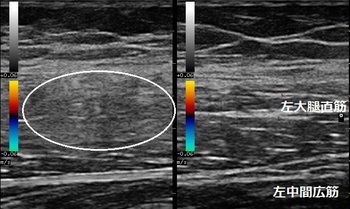

川越市 小学生 もも(大腿)の痛み 筋膜損傷

右もも(大腿部)患部 左もも(同部)正常側 右もも患部3週間後

膝の屈伸をしてもらうと痛みでゆっくりでしかできません。超音波検査で右もも前面の筋肉の

筋周膜(筋肉の縞模様)が正常側に比べて擦り切れ(損傷し)ていました(左画像の丸の囲み)。

小学生は普段サッカー少年団に所属しています。サッカーの練習に加えて、マラソン大会に向けて

ランニングをしていたため筋肉が疲労し、硬くなって筋周膜が擦り切れてしまいました。

筋肉の修復を促し柔軟にする理学療法を行います。日常生活では通学や階段昇降で痛みを

感じなくなるまで運動を休止します。

3週間後、右もも筋肉の筋周膜が修復されてきて、縞模様が視覚的に確認できるようになりました(右画像)。